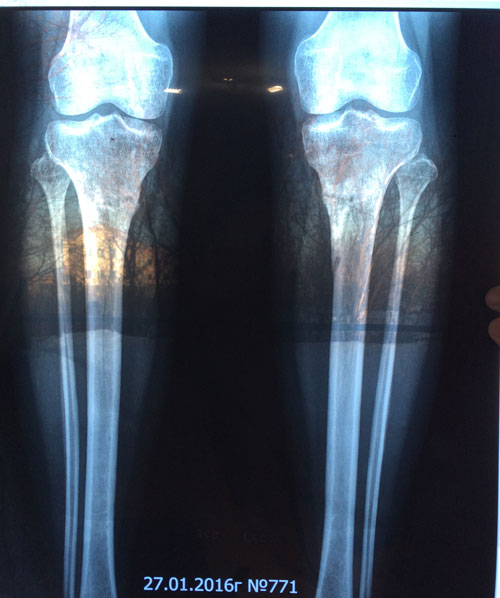

1,5 МЕСЯЦА с момента снятия аппаратов.

Здравствуйте, А.! Сращение железное, ножки в норме. Вы можете ходить на любой вид спорта, фитнеса, каблуки и т.д. Исключить: беременность в первые 6 месяцев с момента снятия аппаратов.